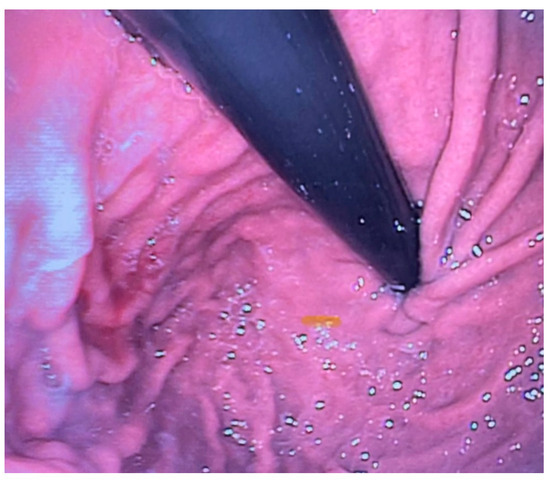

Esophagogastroscopy allowed us to obtain multiple pieces of information in our patients: it allowed us to assess both esophageal and gastric anatomy under direct vision, as well as the contractility of the lower esophageal sphincter. It also provided insights into the macroscopic characteristics of the esophageal and gastric mucosa (Figure 2 and Figure 3). Moreover, by performing at least four esophageal biopsies during each procedure, we were able to confirm the presence of esophagitis and classify its type, which could be a potential consequence of gastroesophageal reflux disease (GERD), using histopathological analysis [9].

Figure 2. Site of the previous esophageal anastomosis with mild caliber reduction and without evidence of stenosis. Good distensibility on insufflation and smooth instrument passage. Mild caliber discrepancy between the upper and lower stumps.